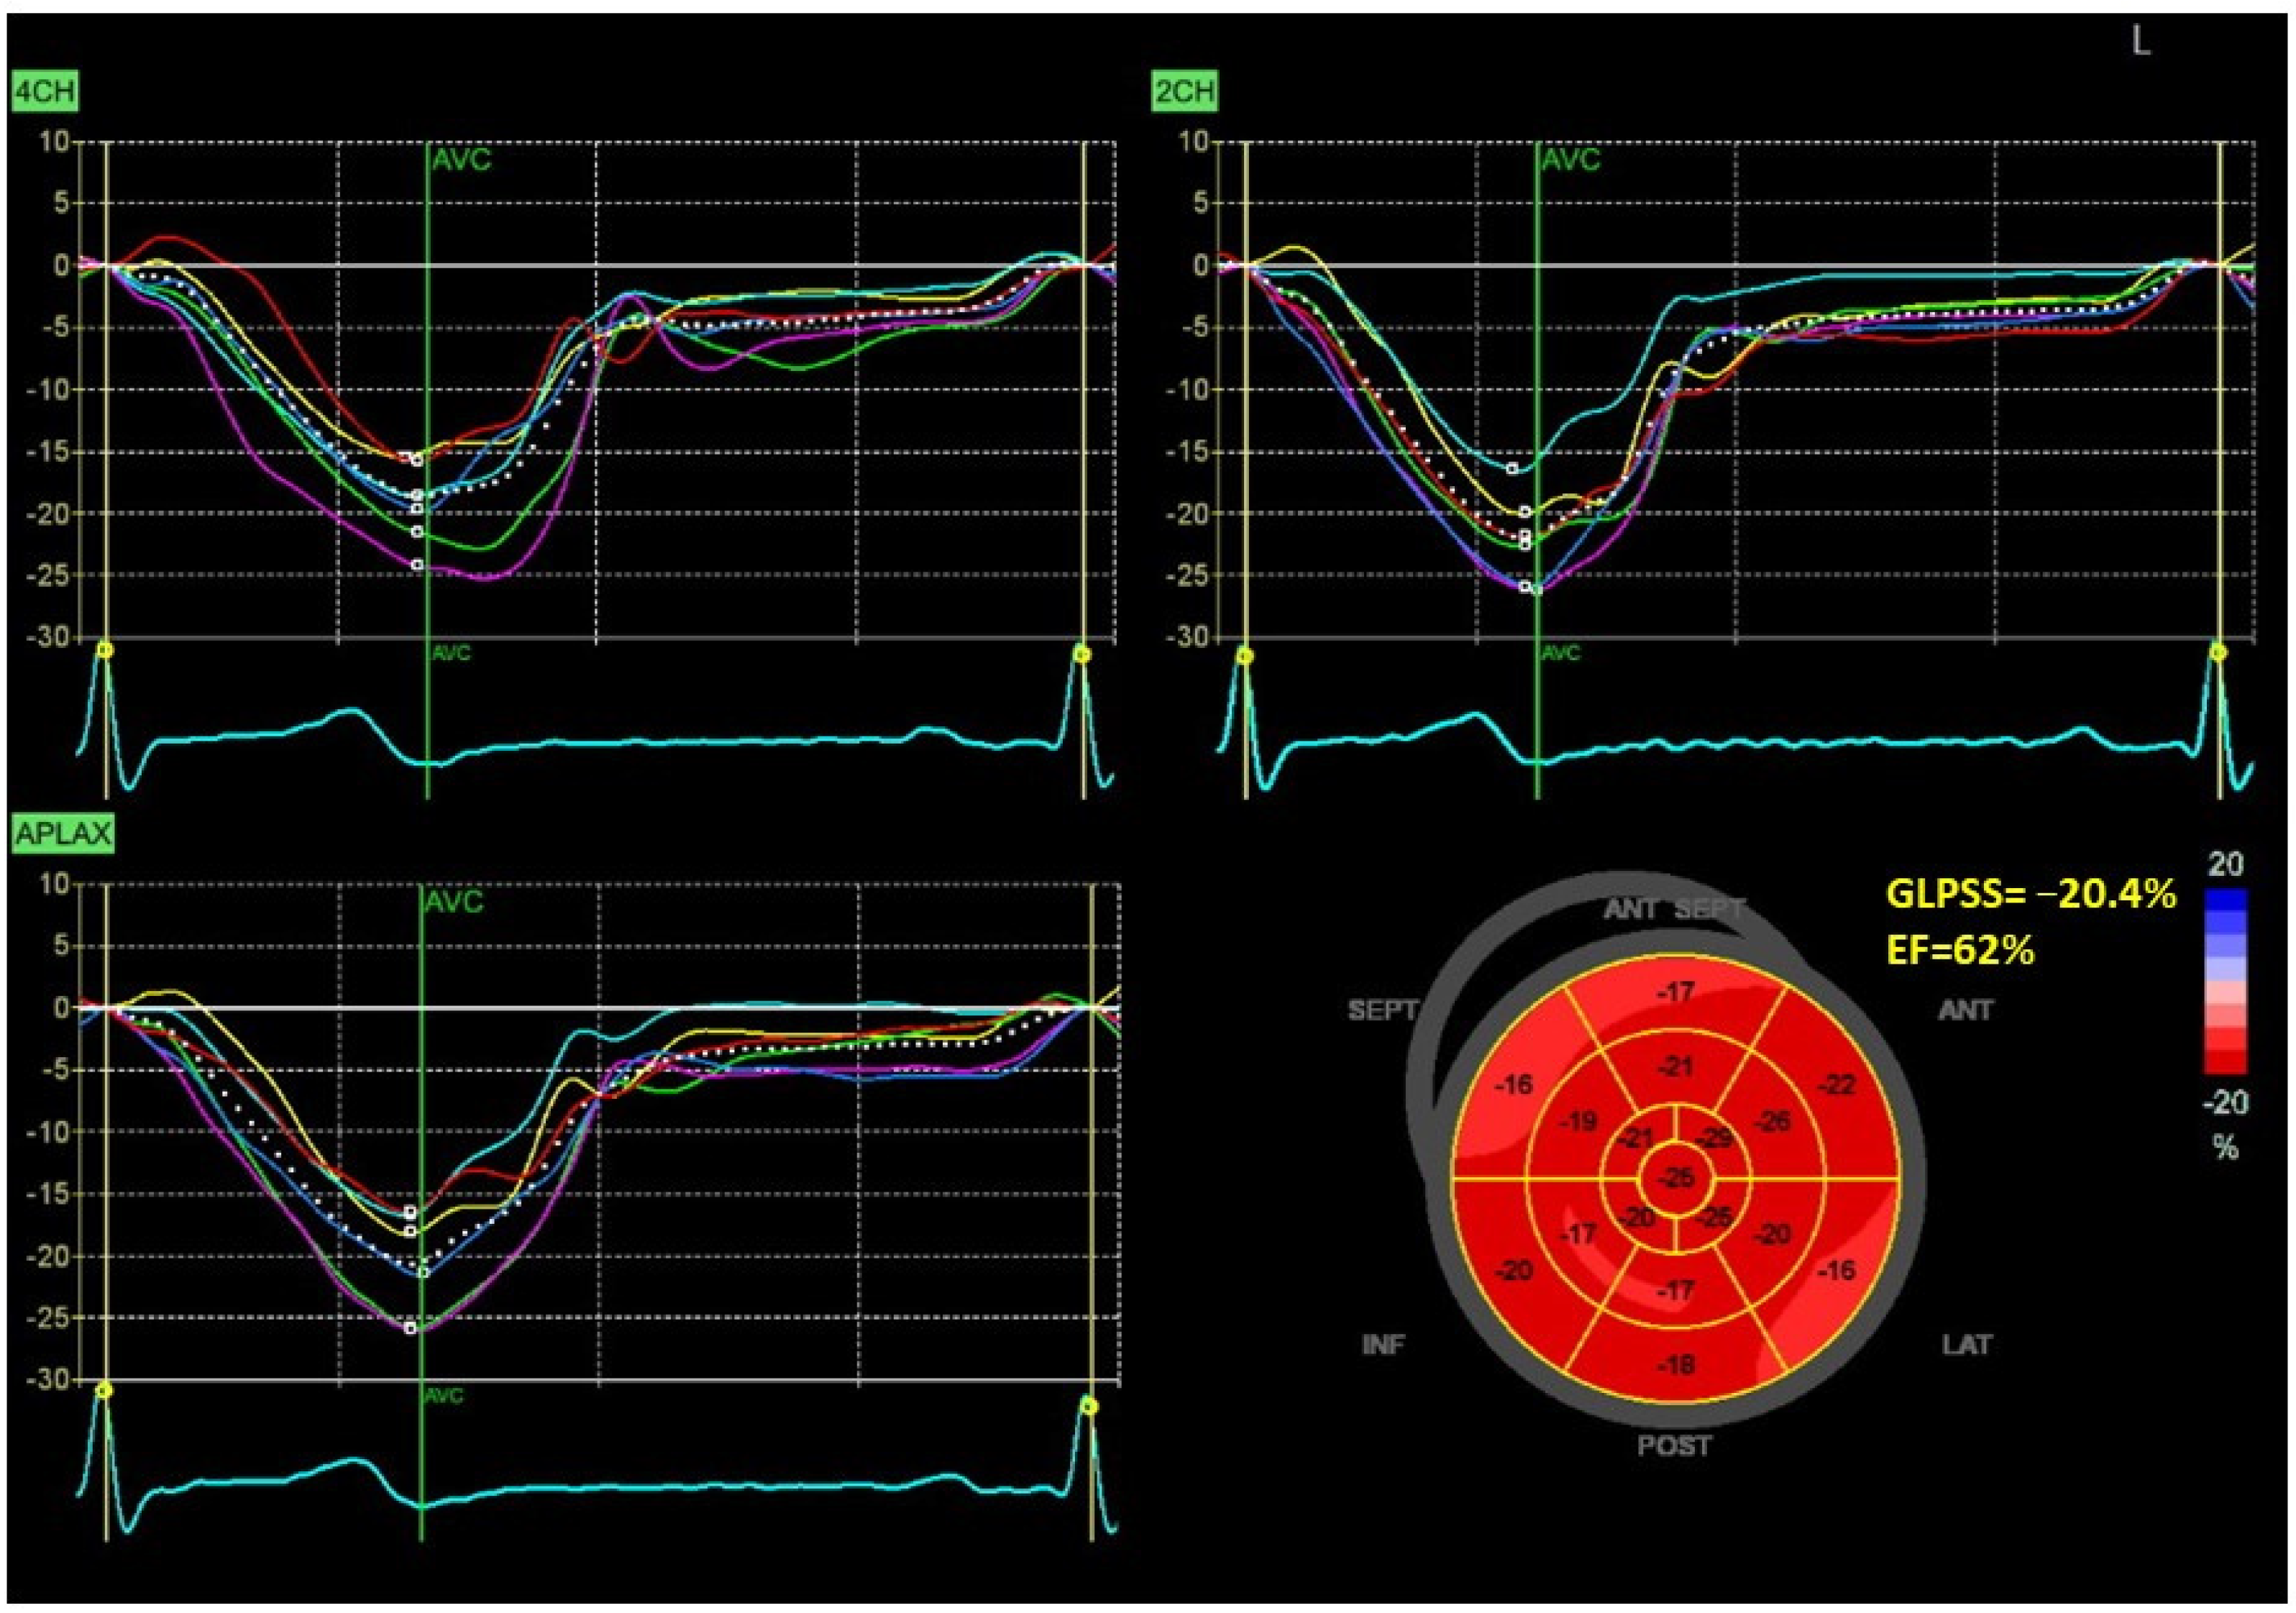

Figure 1 and Figure 2 show two contrasting examples (a healthy person and a patient after myocardial infarction and left bundle branch block) of STE curves with GLPSS, LVEF and LV pressure–strain loops and results of GWE for all LV segments.

Figure 1.

An example of echocardiography of a 30-year-old healthy male. A set of individual longitudinal strain curves for all segments shown in different colors, with the average curve shown as a white dotted line, a bull’s eye of segmental longitudinal peak systolic strains and a summary of global longitudinal peak systolic strain (GLPSS) are shown in the top panel. The LV pressure–strain loop with the bull’s eye representation of myocardial work efficiency for each of the segments and a summary of all myocardial work indices are shown in the lower panel. Abbreviations: GLPSS—global longitudinal peak systolic strain, EF—ejection fraction, GWI—global myocardial work index, GCW—global constructive work, GWW—global wasted work, GWE—global work efficiency, BP—blood pressure.